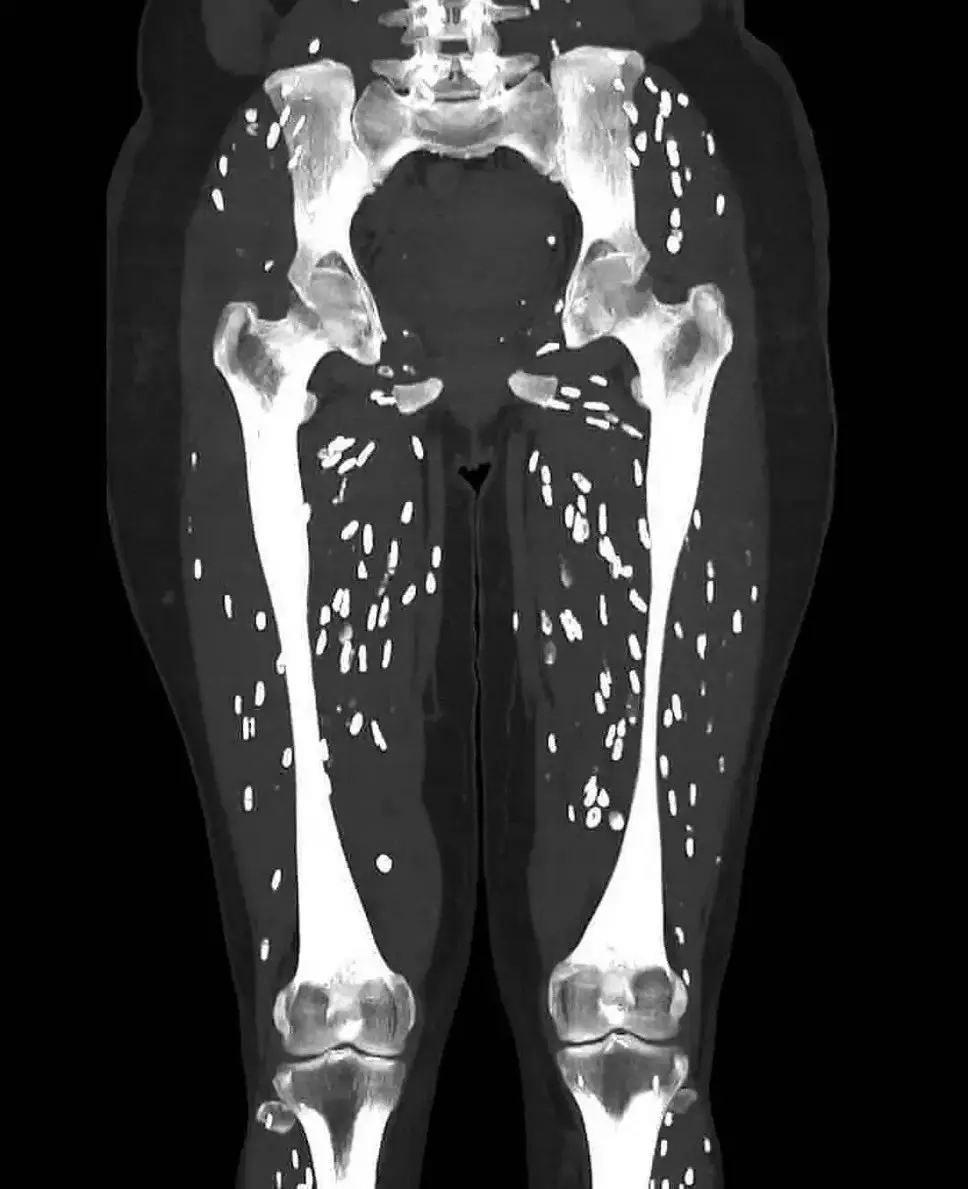

On Sunday (25 August) last week, the medical professional shared a horrifying image of a patient that had eaten contaminated meat, brought on by undercooked or raw pork, on X.

The scan reveals signs of a parasitic infection know as cysticercosis, which is when the larvae of a species of tapeworm enters tissues such as muscles or in the worst cases, the brain.

These form hard calcified cysts that feel like lumps under your skin, and they eerily light up like rice grains on medical scans, scattered all over your body, when it is called cysticerci.